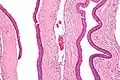

Odontogenic keratocysts have a diagnostic histological appearance. Under the microscope, OKCs vaguely resemble keratinized squamous epithelium;[14] however, they lack rete ridges and often have an artifactual separation from their basement membrane.[2]

The fibrous wall of the cyst is usually thin and uninflamed. The epithelial lining is thin with even thickness and parakeratinised with columnar cells in the basal layer which have focal reverse polarisation (nuclei are on the opposite pole of the cell).[12] The basal cells are an indication of the odontogenic origin as they resemble pre-ameloblasts. The epithelium can separate from the wall, resulting in islands of epithelium. These can go on to form 'satellite' or 'daughter' cysts, leading to an overall multilocular cyst.[9] Presence of daughter cysts is particularly seen in those with NBCCS.[12] Inflamed cysts show hyperplastic epithelium which is no longer characteristic of OKCs and can have resemblance to radicular cysts instead. Due to areas of focal inflammation, a larger biopsy is required for correct diagnosis of odontogenic keratocysts.[9]

Intermediate magnification of an odontogenic keratocyst showing a folded cyst.

Intermediate magnification of an odontogenic keratocyst